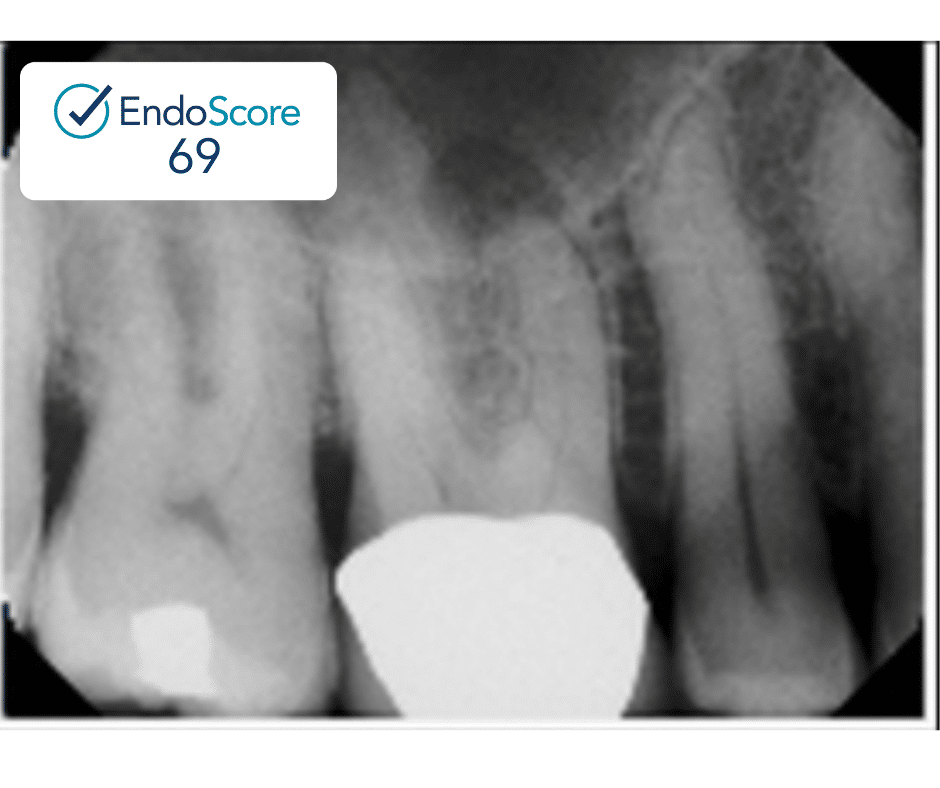

Case Study by Dr. Justin Kolnick

Endoscore of 69 was reduced to a final score of Endoscore 1 after MB2 canal was located and treated.

Obturated with EndoCeramicâ„¢ Sealer (Endo Direct) and single cone gutta percha.

EndoScore: 69 to 1